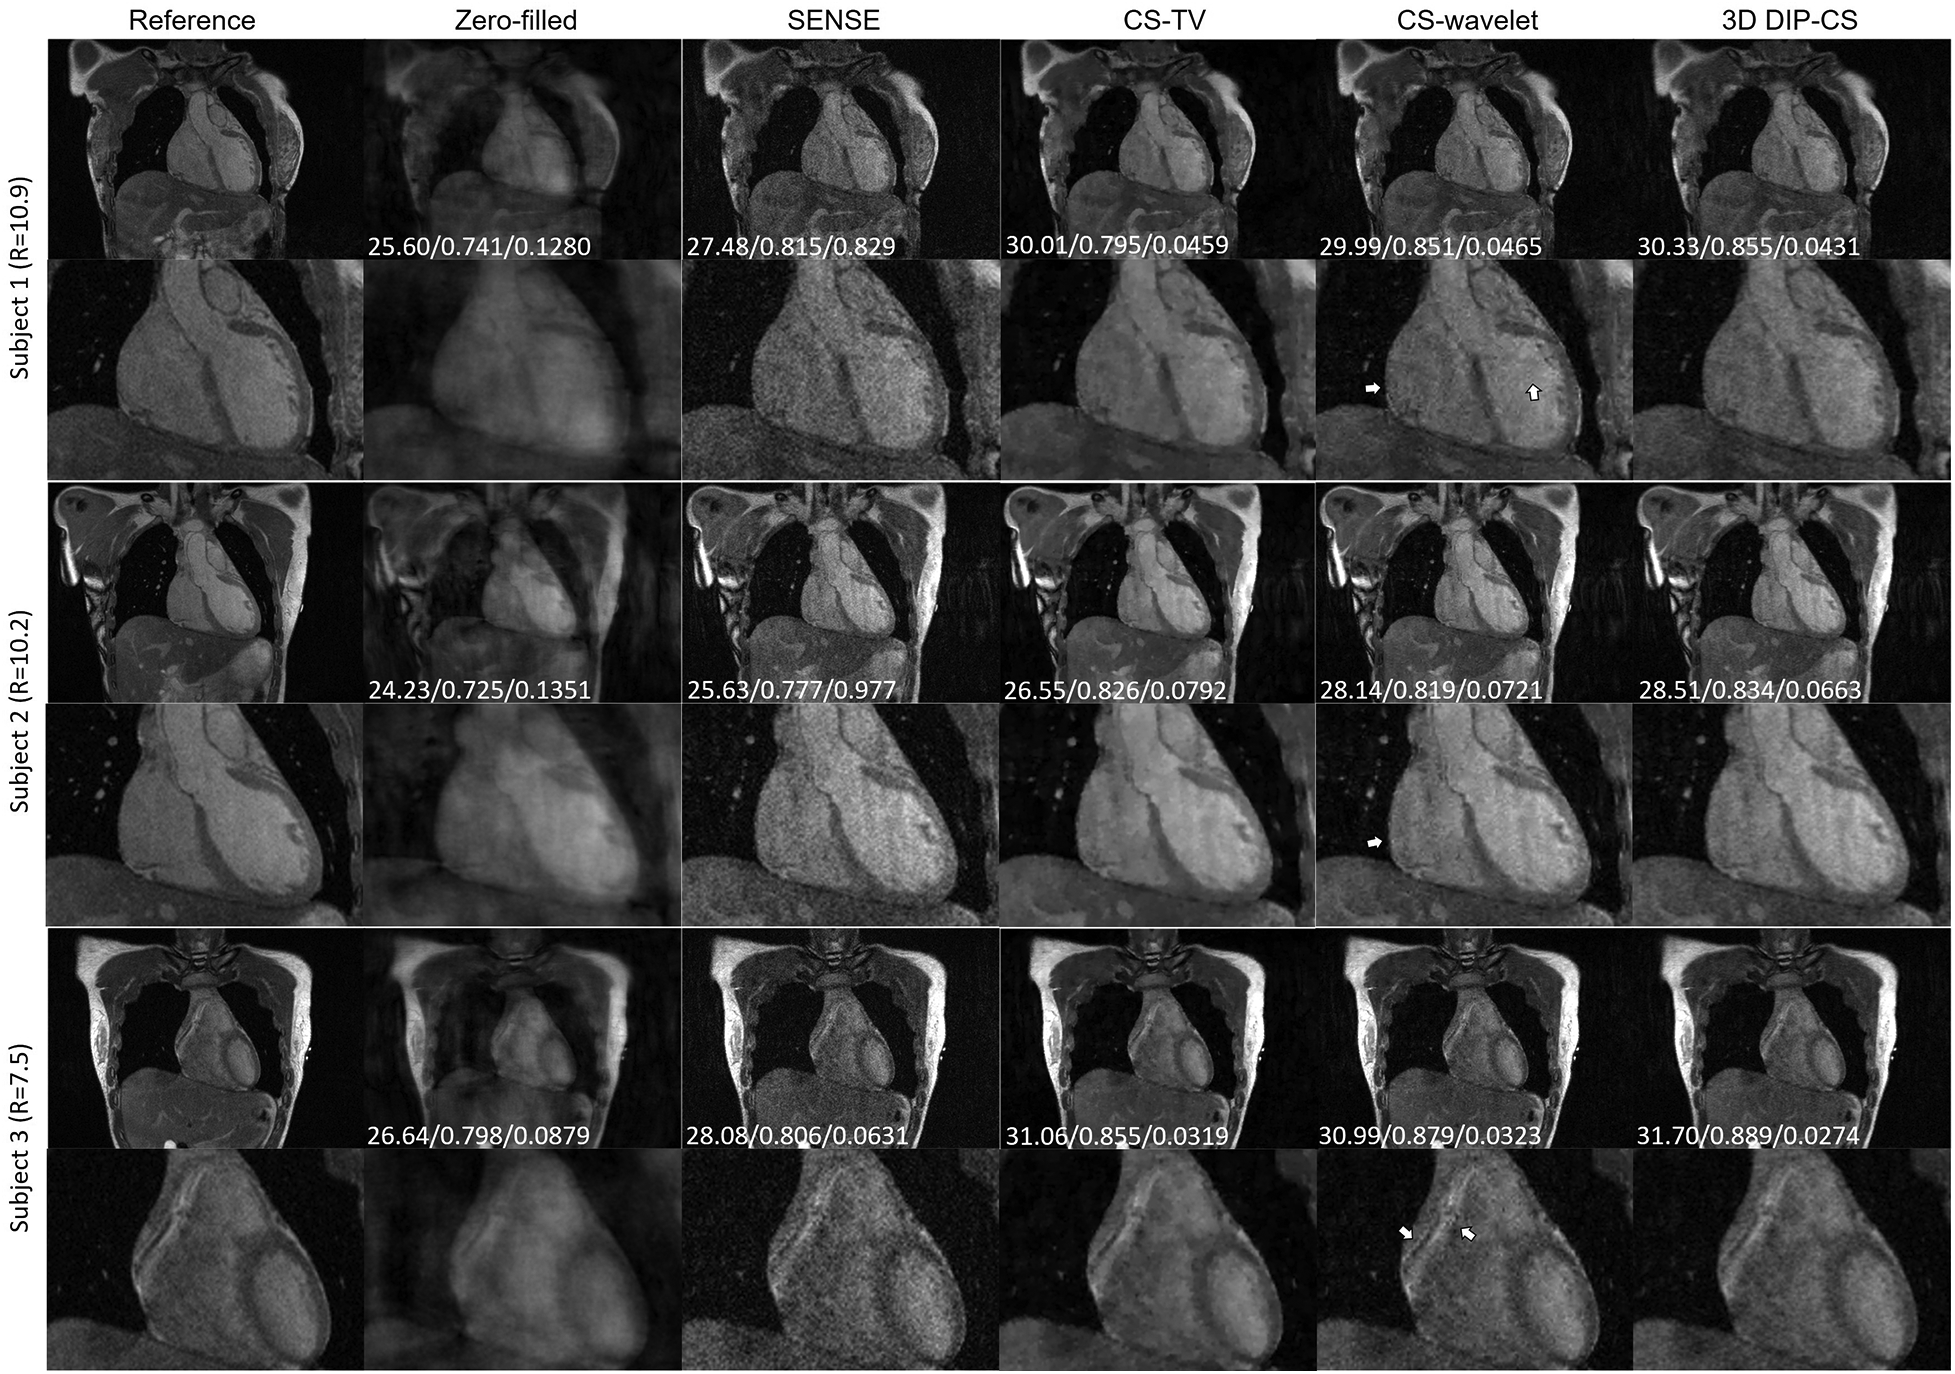

4.3 Imaging with prospective accelerations

We assessed our method using real CMRA data acquired within 5 min, which had an acceleration factor of 7–11. An image reconstructed from a 15 min scan was used as the reference. Figure 9 shows a representative result. SENSE and CS-based methods were able to give reconstructions with reduced undersampling artifacts compared with zero-filling. However, noise appeared stronger in the SENSE reconstruction compared to the other methods. CS-TV significantly suppressed the noise but caused visible blurring in the images. CS-wavelet reconstructions mitigated some noise and undersampling artifacts; however, the images still showed some unsmooth features compared with the reference image (indicated by the white arrows in Figure 9). The 3D DIP-CS method removed most of the artifacts and well suppressed the noise, generating an image quality more similar to the reference image. Table 3 quantitatively compared the image quality metrics among these methods with respect to the 15 min reference images. DIP-CS achieved significantly higher PSNR, SSIM, and lower NMSE compared to classical CS-wavelet (PSNR: P = 0.001; SSIM: P = 0.015; NMSE: P = 0.001).

Figure 9

Reconstructions (in the coronal view) obtained using zero-filling, iterative SENSE, CS-TV, CS-wavelet and 3D DIP-CS from data acquired in five minutes. White arrows indicate the unsmooth details in the zoomed out images. PSNR, SSIM, and NMSE were given at the bottom of each image.